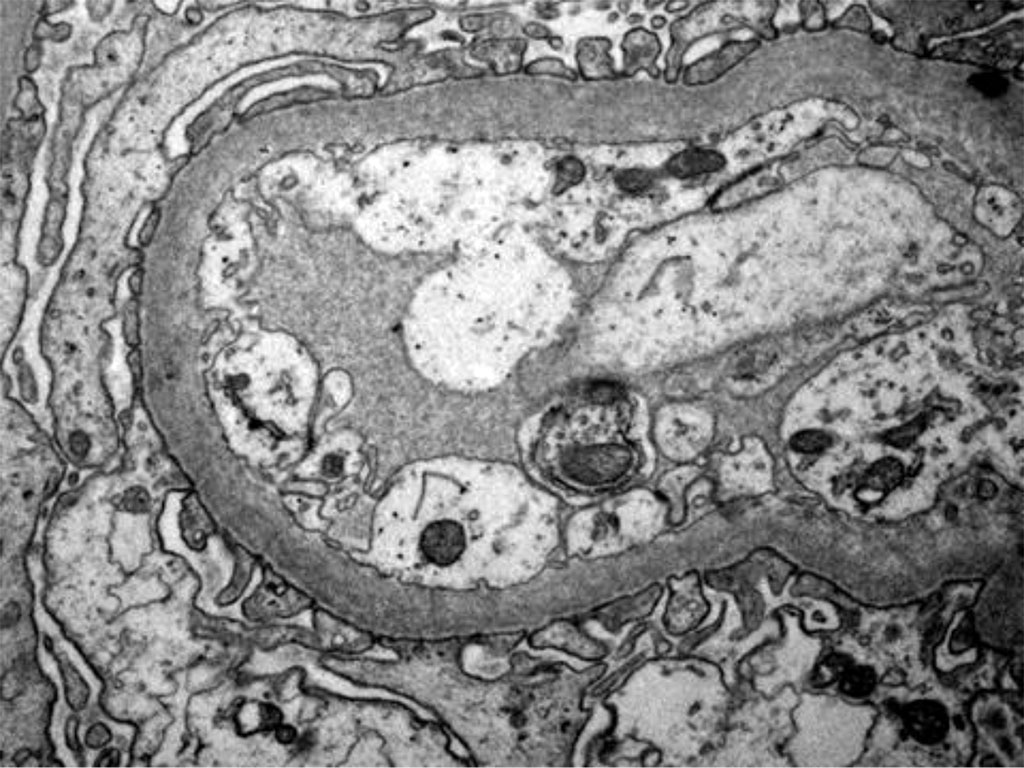

Figure 4. Electron microscopy - Podocytes foot process effacement

Figure 5. Electron microscopy - Podocytes foot process Effacement

An important way to confirm hantavirus infection is by renal biopsy. The histological findings in hantavirus nephritis are peritubular capilaritis without important tubulitis and hemorrhage is limited in the medulla [5]. Interstitial oedema and inflammatory cell infiltrates (lymphocytes, monocytes, macrophages and polymorphonuclear leucocytes) are usually seen. In electron microscopy, podocytes foot process effacement was described in some studies with hantavirus infection [9,10]